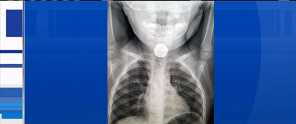

Toddler Saved by Parents' Persistence to find Lithium Battery Stuck in Esophagus

An x-ray provided the problem and solution easily, but the path to it was not so easy, and could have had tragic results had it not been for the persistence 2-year-old Katie Smith's parents:

According to Smith, the first four doctors said Katie likely had a flu or cold, but a fifth doctor at Toronto's Hospital for Sick Children ordered X-rays and discovered what was actually wrong: A small, circular, foreign object was lodged in Katie's esophagus, the tube that connects the mouth to the stomach.

"At first there were mentions of a plastic bottle cap, and then a coin, but then we got on the phone with an ear, nose, and throat specialist who said it could be a button battery," Smith said.